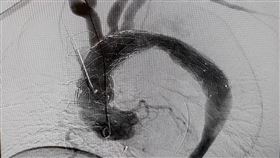

未爆彈!6.5cm「主動脈瘤」隨時索命

花蓮一名50多歲廖先生中風多年,去年因急性A型主動脈...